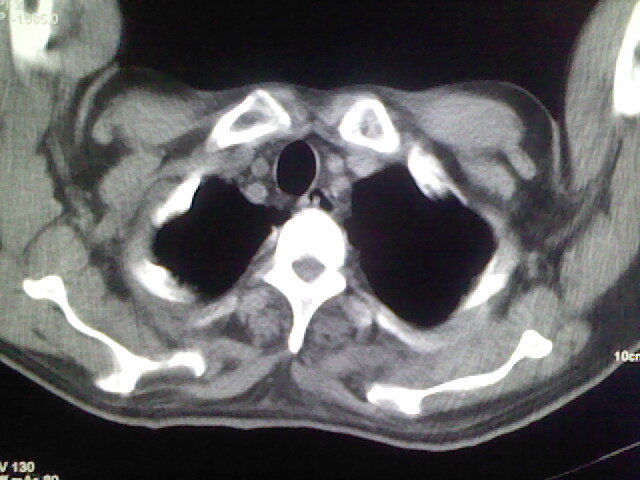

男,70岁,脑出血,长期卧床,左侧背部可触及肿块

肺部感染,背部筋膜增厚,考虑坠积性水肿或炎症

右侧肺部见片状密度增高影,边缘模糊。考虑炎症。另食管壁增厚。